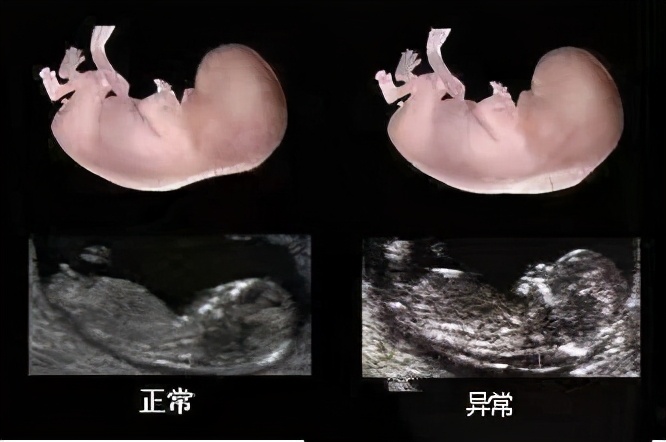

首先,孕妈妈需要明白,四维彩超是一种噱头,在我们医学上称为胎儿超声彩超,有I级超声(一般产前超声检查)、II级超声(常规产检超声检查)、III级超声(系统产前超检查)及IV级超声(针对性彩超)。Ⅰ级产前超声检查,用于评估胎儿大小、胎方位、羊水、胎盘等一般评估胎儿生长指标的检查,不进行胎儿解剖结构和胎儿畸形的筛查。II级超声是用于排除胎儿致死性畸形,如:无脑儿、严重的脑膨出、严重的开放性脊柱裂、严重胸、腹壁缺损、内脏外翻、单腔心、致死性软骨发育不良等情况的检查,同时还对胎儿主要脏器进行形态学的观察,比如胎儿脊柱、四腔心切面、腹部脏器(肝、胃、肾、膀胱)等。I级和II级超声都是产前筛查的超声检查。III级超声和IV针对性超声是在有产前诊断的医院开展的超声检查。IV级针对性超声检查通常要在前面检查的基础上才能开展,针对胎儿、孕妇特殊问题进行特定目的的检查,如胎儿超声心动图检查、胎儿神经系统检查、颜面部针对性超声检查、 胎儿四肢超声检查等。

一般孕妇可以行II级超声及可以,但是高危孕妇或者有产前诊断的孕妇,建议行III级彩超。但是如II级或者III级彩超发现异常,应该建议行胎儿IV级针对性彩超。

胎儿产前超声检查有两个重要的时间:孕周20-24周和孕28-34周,即我们所谓的“大排畸”和“小排畸”。而其中大排畸最为重要,孕妈妈千万不要错误。